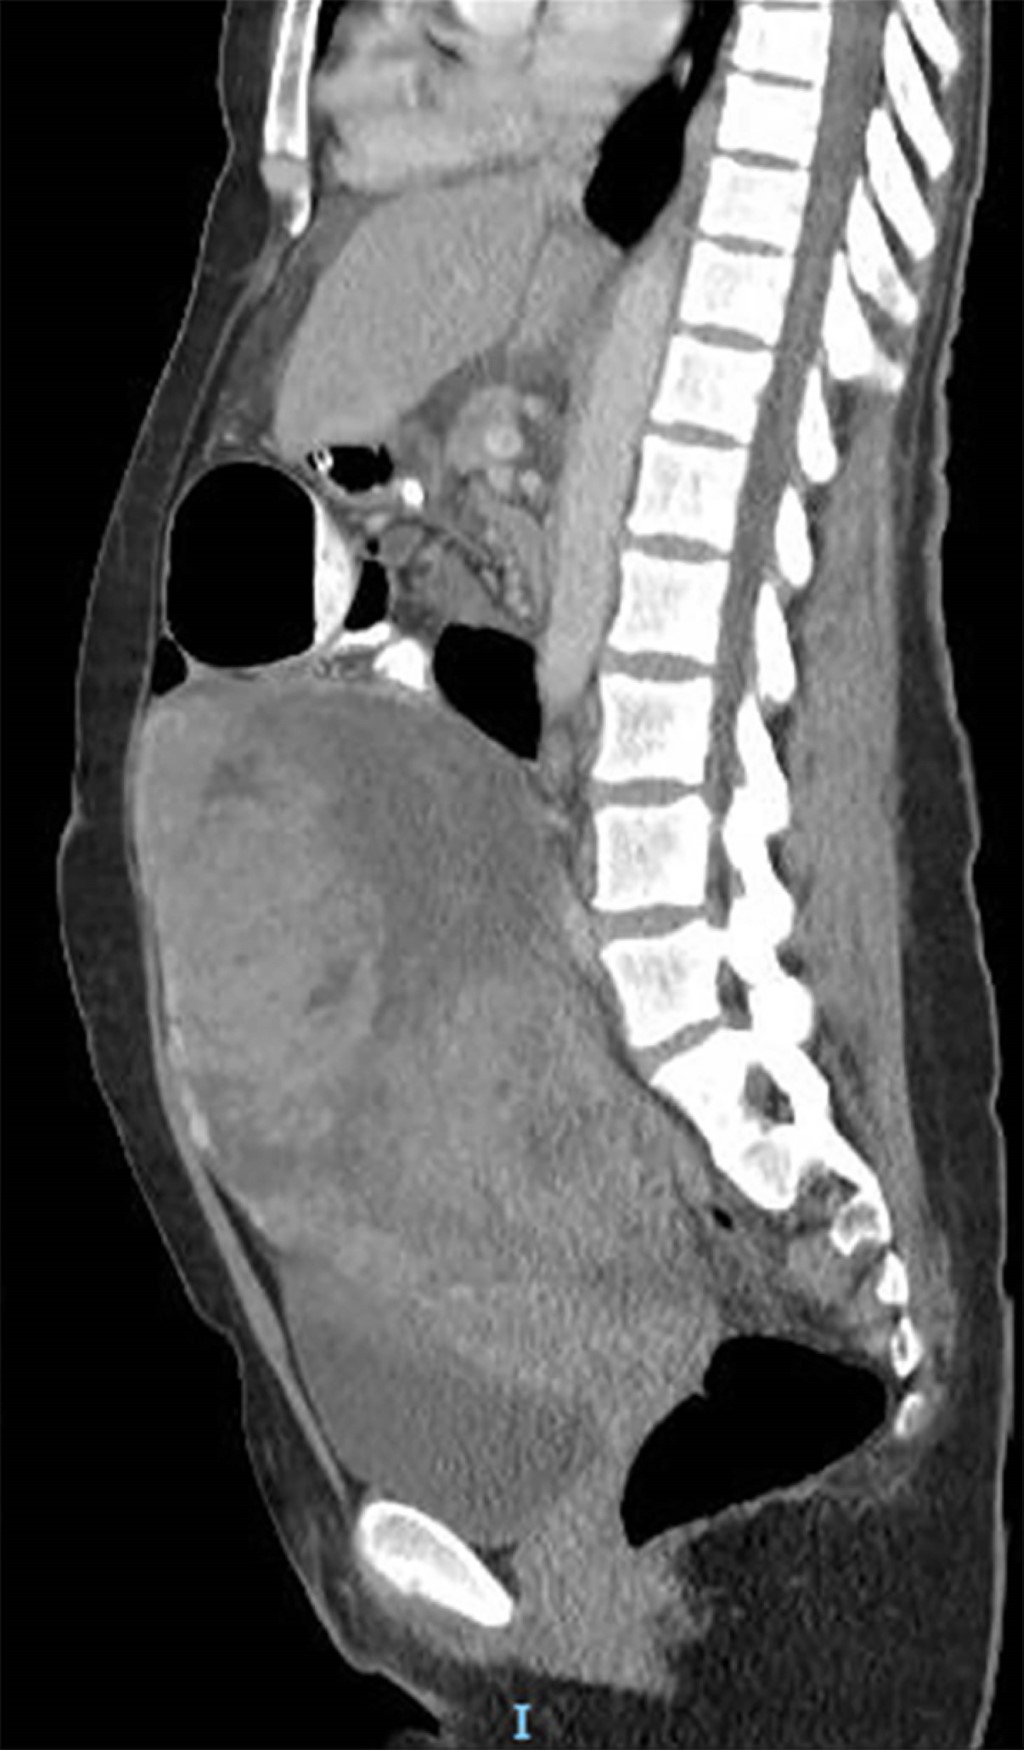

Se presenta una mujer de 51 años, con antecedentes de VIH sin adherencia al tratamiento antirretroviral, quien consultó por dolor abdominal difuso de tres meses de evolución y constipación en los últimos 10 días. En el examen físico, se evidenció abdomen distendido con falta de eliminación de gases sin signos de irritación peritoneal. Presentaba un tumor palpable en hipogastrio que se extendía hasta la región umbilical. En el laboratorio se objetivó una elevación del antígeno CA-125 (153 U/mL; valor normal hasta 35 U/mL), con el resto de las determinaciones dentro de los parámetros normales. La tomografía abdominopelviana con contraste oral y endovenoso reveló una voluminosa formación centro pélvica de 28 × 12 × 12 cm asociada a ascitis, distensión del marco colónico y progresión del contraste oral hasta colon sigmoides (Figuras 1 y 2).

Figura 2